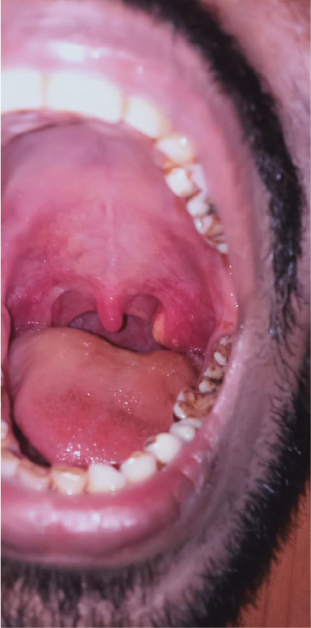

A 32-year-old male presented to the ENT OPD with enlargement of the left tonsil since 3 to 4 years with off and on increase in the size of the swelling coinciding with bouts of upper respiratory infections (URI) (Fig. 1). During the URI episodes, the patient also complained of odynophagia, halitosis and a raw sensation in the throat and fever. He relied on home remedies to get relief from these symptoms.

Figure 1. Patient’s intraoral picture showing enlarged tonsil on the left side with a prominent yellowish growth on upper pole of tonsil.